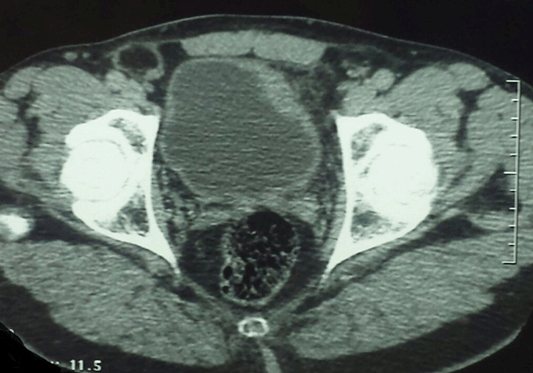

Cursor on image to zoom/Click text to open image

Figure 1: Computed tomography scan of the pelvis in axial view demonstrating a thickening of the left anterolateral wall of the bladder.